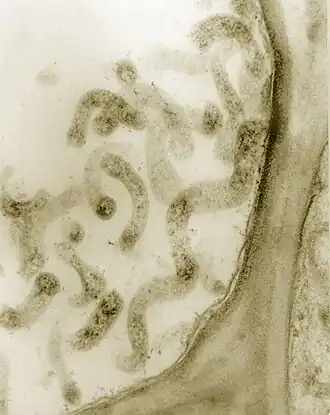

Микопла́змы (лат. Mollicutes) — класс бактерий, одноклеточных микроорганизмов[1][2], не имеющих клеточной стенки, которые были открыты при изучении плевропневмонии у коров. Микоплазмы, по всей видимости, являются наиболее низкоорганизованными самостоятельно воспроизводящимися живыми организмами, объём их генетической информации в 4 раза меньше, чем у Escherichia coli.

Микоплазмы отличаются от остальных бактерий отсутствием жёсткой клеточной стенки (в результате чего от внешней среды их отделяет лишь цитоплазматическая мембрана) и ярко выраженным полиморфизмом.

В культуре одного вида можно выделить крупные и мелкие шаровидные, эллипсообразные, дисковидные, палочковидные и нитевидные, в том числе ветвящиеся (из-за этого все микоплазмы одно время причислялись к актиномицетам) клетки. Описаны и разные способы размножения: фрагментация, бинарное деление, почкование. При делении полученные клетки не равноценны по размеру, часто одна из них даже нежизнеспособна. К микоплазмам относятся формы с самыми мелкими из известных клеточных микроорганизмов размерами, в том числе меньше теоретического предела самостоятельного воспроизводства на питательной среде (этот предел для сферических клеток составляет 0,15—0,20 мкм а для нитевидных — 13 мкм в длину при 20 нм в диаметре).